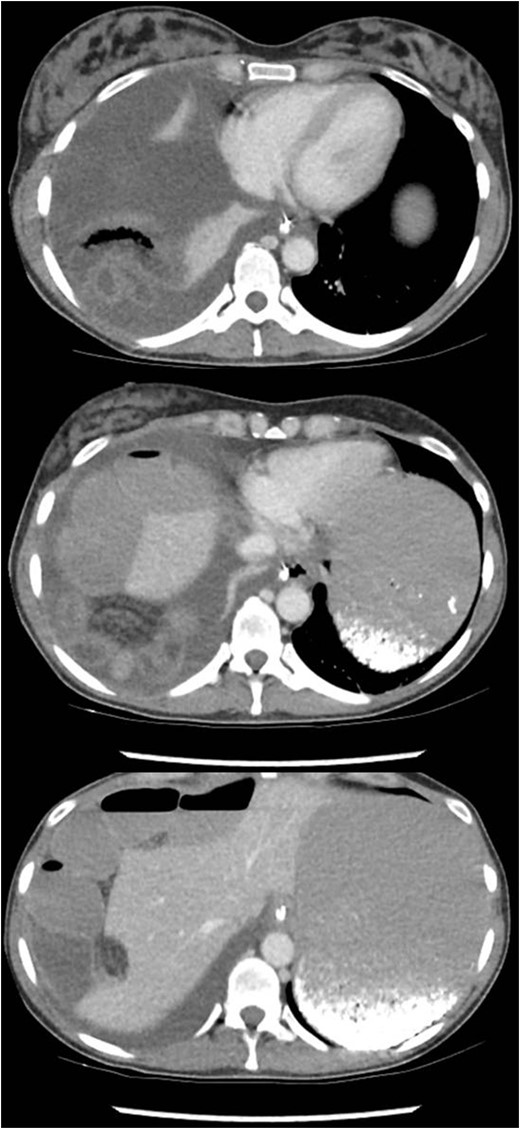

A healthy 41-year-old female, 38-week pregnant, presented with irretractable abdominal pain and vomiting. There was no previous similar history or abdominal surgery. She associated the onset of symptoms with a low energy fall on to her buttocks. There was no improvement despite hastening her elective caesarean section. Thereafter, she was treated as a post-operative ileus (Fig. 1). On multiple examinations, she remained afebrile and haemodynamically stable. The abdomen was distended, with generalized mild tenderness. Bowel sounds were audible. Blood tests were unremarkable. Failure to progress prompted further evaluation with CT. This revealed a small bowel obstruction secondary to a right-sided diaphragmatic hernia (Fig. 2). After resuscitation, she proceeded to laparoscopy.

A 10 mm port was inserted infraumbilically using Hasson technique, with an additional three operating ports. Laparoscopy confirmed radiological findings of a right-sided diaphragmatic defect with herniation of terminal ileum.